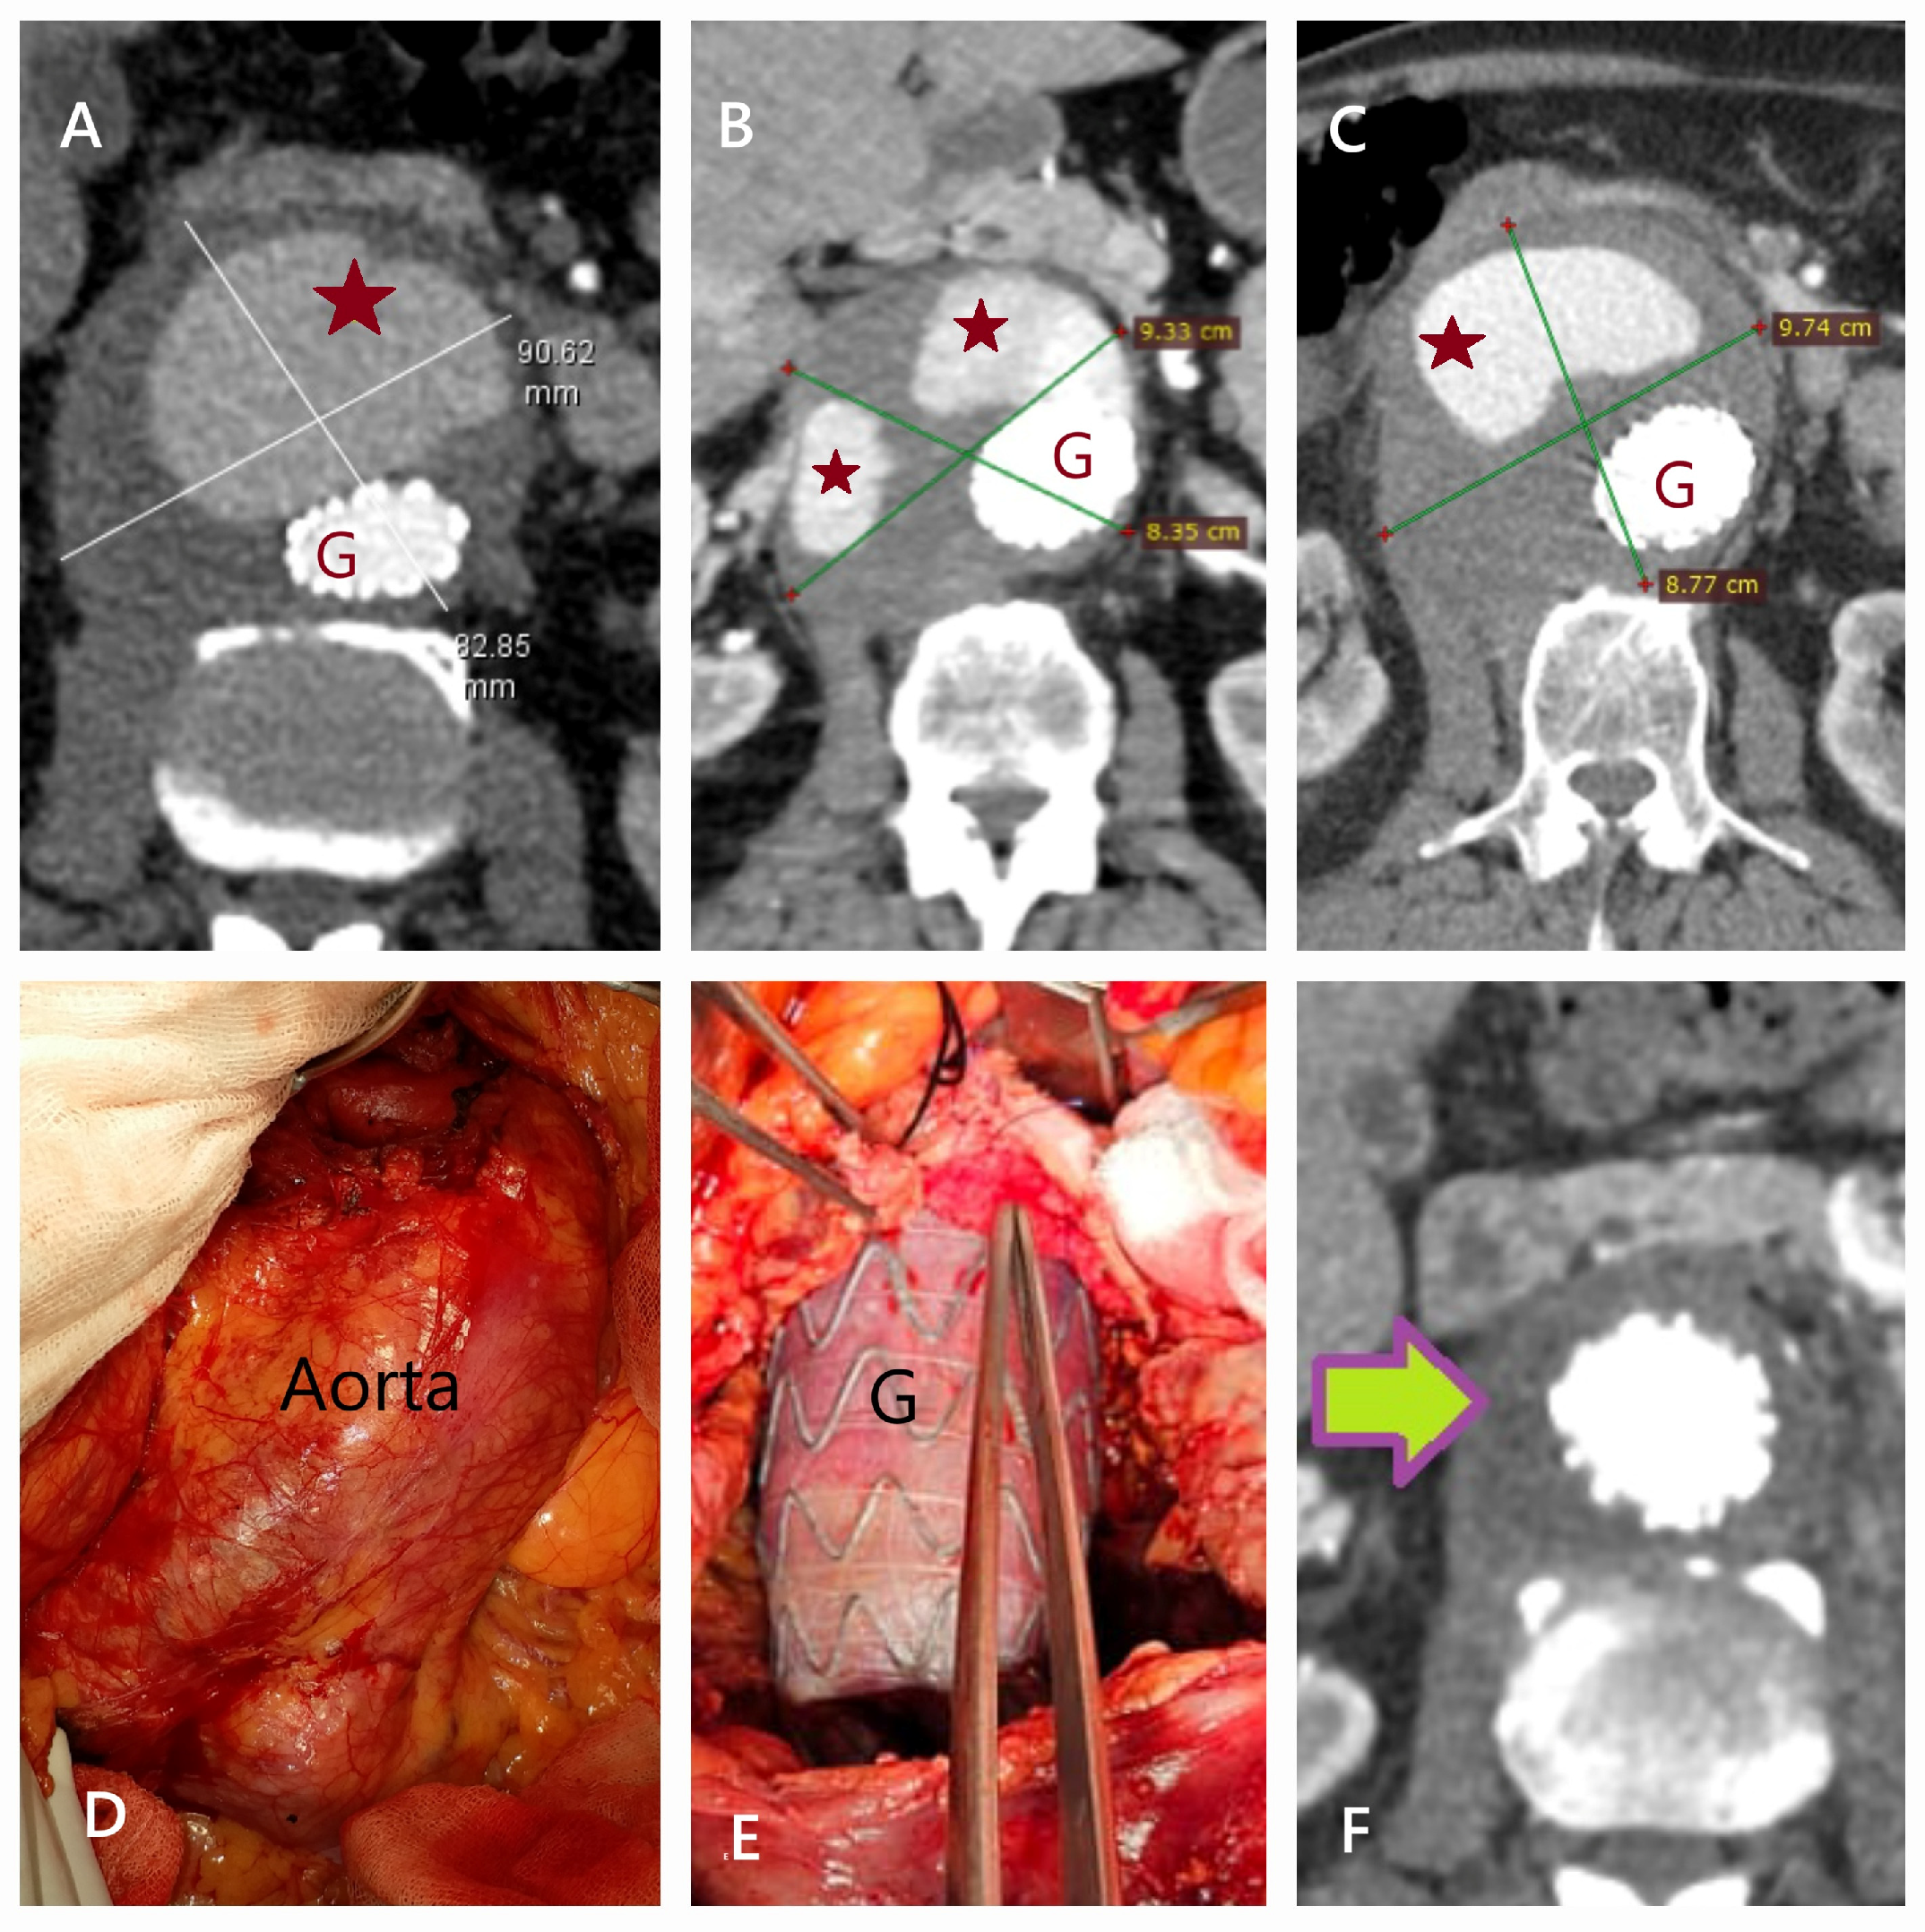

2.6. EVAR Technique

2.7. Open Surgical Repair Technique

5.1. Failure of EVAR

5.2. Conversion to Open Surgery